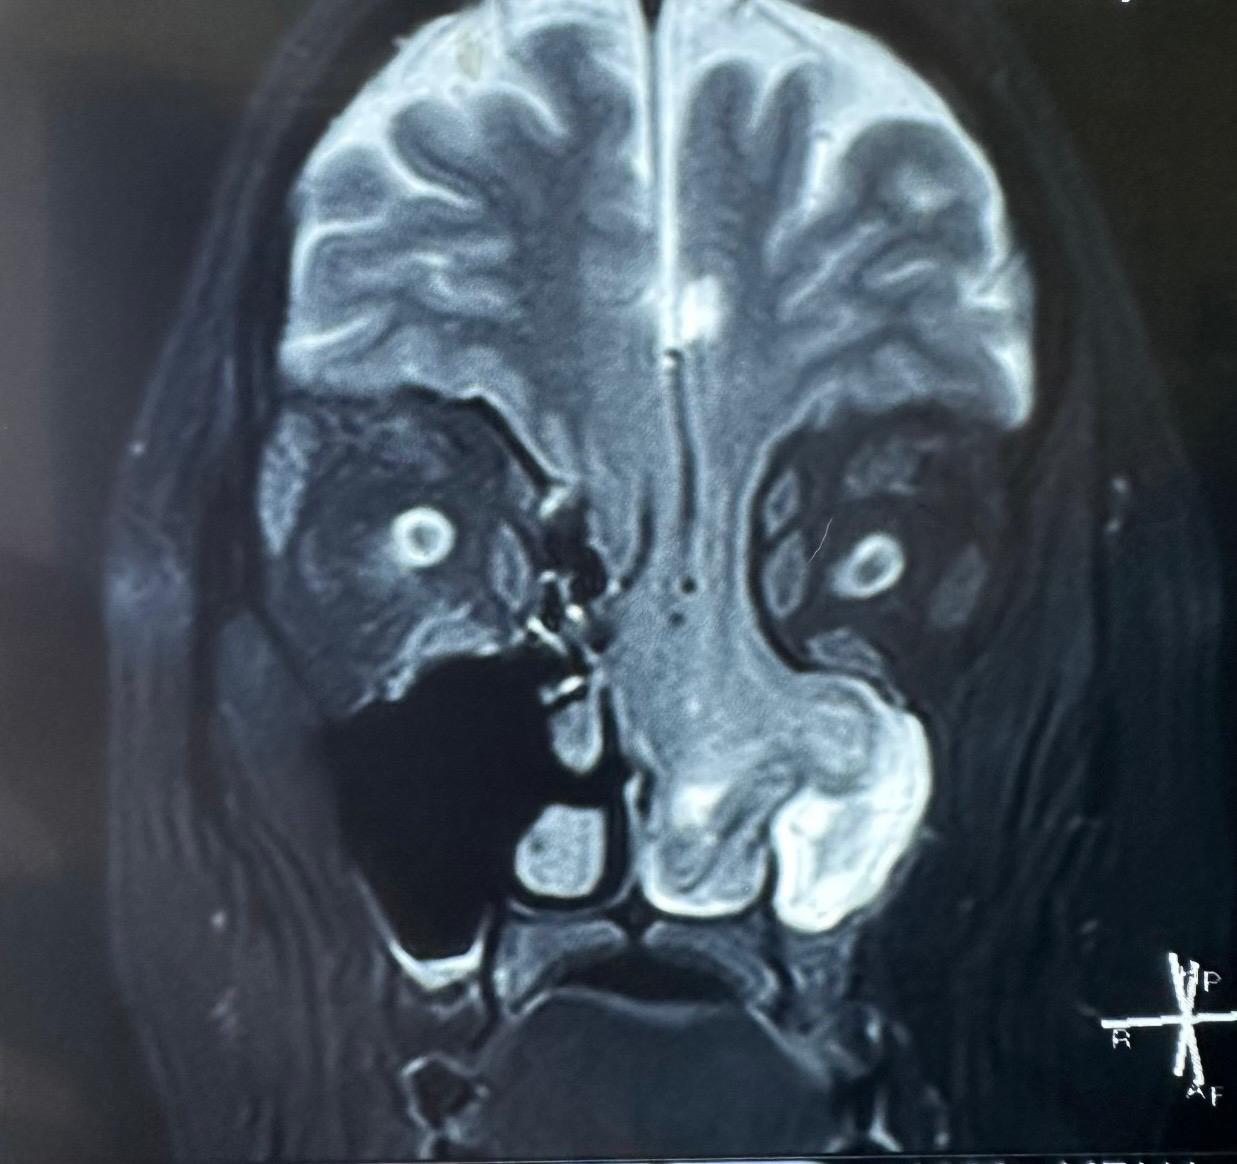

Dr. Ashish Vashishth, HOD & Consultant – ENT (Otorhinolaryngology, Head and Neck and Cranial Base Surgery, Ear, Nose and Throat) said, “When the patient came to us with persistent nasal obstruction, an initial endoscopic examination in our ENT department raised suspicion of a rare condition. Targeted CT and MRI scans revealed that part of her brain had herniated through the eroded skull base into the nasal cavity. This case certainly highlights the importance of a thorough diagnostic pathway and consulting the right specialists at the right time. What made this case challenging was the technical precision needed to manage such a delicate and high-risk cranial base reconstruction. The success of this case truly highlights the strength of a multidisciplinary and diagnostic-first approach.”

Dr. Anurag Saxena, Cluster Head-Delhi NCR, Neurosurgery, said, “This was an extremely rare and technically demanding case. The patient was at significant risk of developing a life-threatening stroke, as the brain’s blood vessels were also herniating down along with the brain tissue. Even the slightest injury to these vessels could have caused devastating complications. Almost half of the frontal and basal parts of the brain were hanging down through the skull base defect, which made performing the surgery exceptionally complex. Through a carefully coordinated endoscopic and transcranial approach, we successfully repositioned the brain, reconstructed the skull base, and ensured her safe recovery. The patient has now recovered well and is leading a normal life under regular follow-up care.”